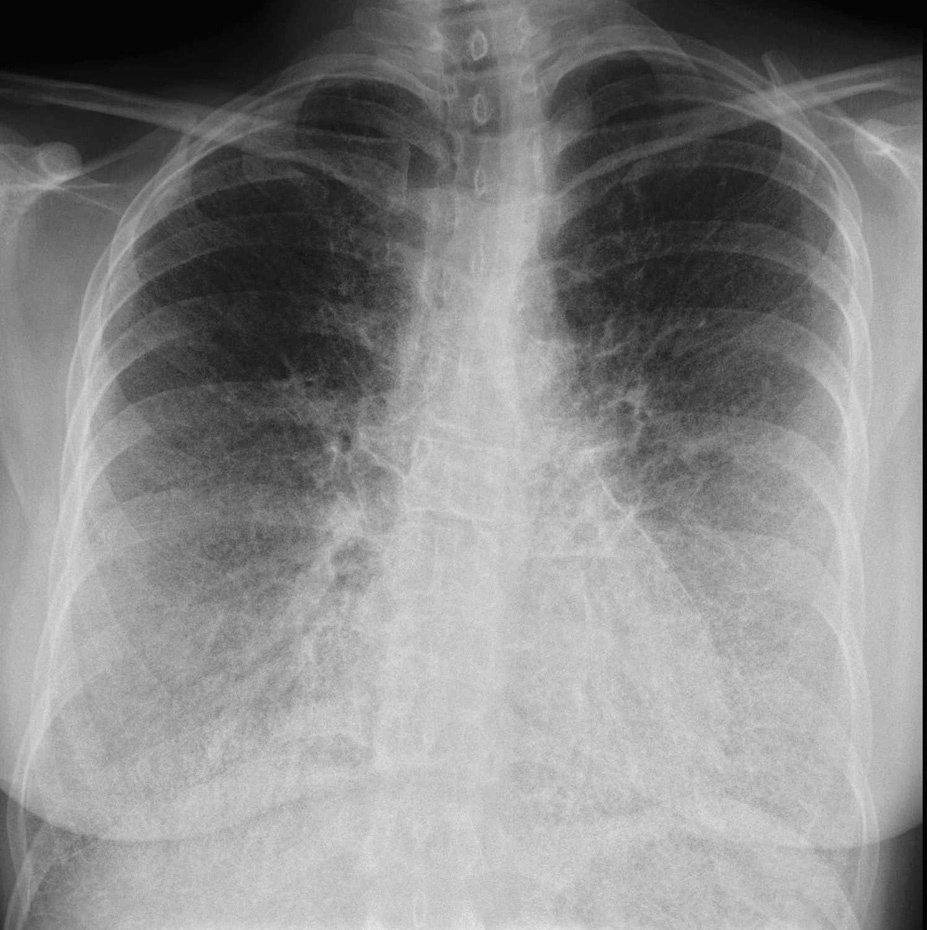

La radiografía de tórax muestra un patrón reticular bilateral mal definido con mayor afectación de bases (fig. 1), y se observa en el perfil una línea radiolucente subpleural anterior.

Fig. 1. En la radiografía de tórax anteroposterior se visualizan marcadas opacidades lineales reticulares bilaterales y difusas, con mayor afectación de bases pulmonares.